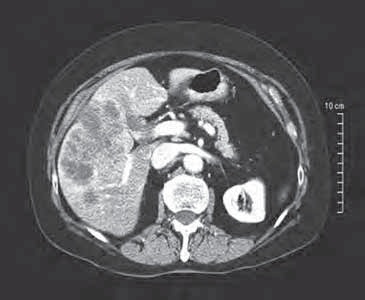

如果病人事先进行静脉化疗,局部肿瘤控制(无进展)是40-86%;然而首次DEB-TACE术后,PFS和 OS分别是有限的4-8.1个月和5.4-13.3个月。 应用荷载伊立替康微球的经导管栓塞,可以在相当的比例下获得结直肠癌肝转移病灶血管几近消失。据报告【25】,使用伊立替康荷载的微球栓塞,肝转移病变经增强CT扫描,在第三个月染色完全消失的为7/29例,肿瘤容积≥50%肿瘤坏死为14/29%。在药物、栓塞剂和微球方面,选择与非选择应用没有标准。

术前:肝左右叶肝转移癌

伊立替康荷载微球栓塞

两次TACE术后随访:首次TACE术后病人存活12个月